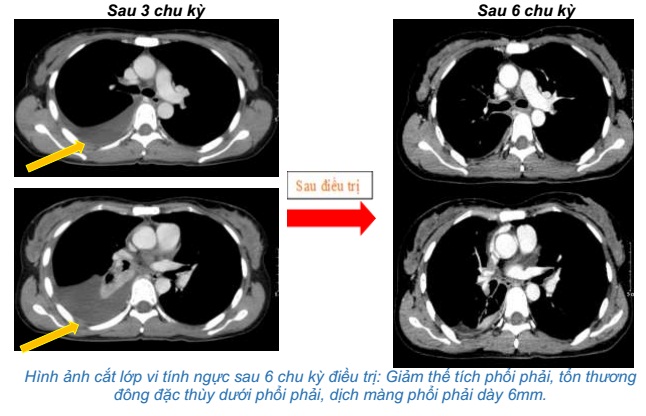

- Chụp cắt lớp vi tính ngực:Khối vùng rốn phổi phải gây xẹp phổi kích thước 28x32mm. Dịch khoang màng phổi phải dày 50mm. Khống thấy hạch to trung thất

So sánh hình ảnh cắt lớp vi tính ngực trước và sau điều trị 3 chu kỳ:

- Chụp cắt lớp vi tính ngực:Giảm thể tích phổi phải, tổn thương đông đặc thùy dưới phổi phải, dịch màng phổi phải dày 6mm.

Sau 6 chu kỳ điều trị:

Sau điều trị hoá trị kết hợp Pembrolizumab cho thấy: U phổi giảm kích thước, hạch trung thất không còn, chất chỉ điểm khối u CEA, Cyfra 21-1 giảm về giới hạn bình thường, tổn thương di căn gan các nốt nhu mô gan giảm bớt. Bệnh nhân không gặp tác dụng phụ đáng kể nào trong quá trình điều trị.